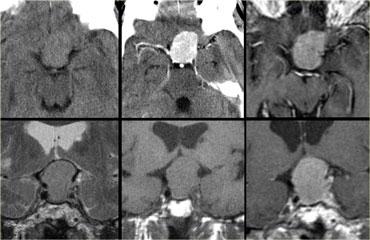

Hình ảnh chuỗi xung T1W và T2W mặt phẳng coronal, cùng với hình ảnh chuỗi xung T1W trước và sau tiêm gadolinium.

Ở bệnh nhân này, tổn thương trong tuyến yên chỉ có thể phát hiện được sau khi tiêm thuốc tương phản từ đường tĩnh mạch.

Chẩn đoán phân biệt: u tuyến yên vi thể hoặc nang khe Rathke.